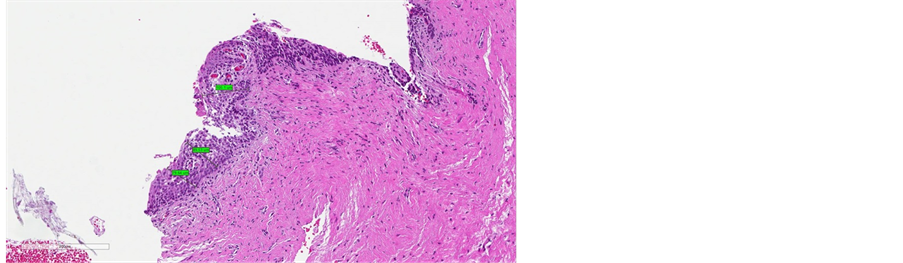

Before treatment, the stratified squamous epithelium appeared atrophic and thin, with no evidence of the crests of the Malpighian layer and epithelial papillae, and with a flattened sub-epithelial junction (Figure 4(a), Figure 5(a), Figure 6(a)). Post-treatment histology samples showed restoration of the epithelial and subepithelial structures, characteristic of reproductive-age vaginal mucosa

(Figure 4(b), Figure 5(b), Figure 6(b)). Immunostaining for collagen III and IV demonstrated a visible post-treatment enhancement. Microscopic examination of the biopsy sections revealed a striking increase in the thickness of epitelium, with resurfacing of the Malpighian layer and epithelial papillae. The median improvement from baseline in epithelium thickness was 97% (range: 9% - 203%).

Figure 5. (a) pre-treatment measures (from minimum measure of 79 µm to maximum measure of 103 µm); (b) post-treatment measures (from minimum measure of 200 µm to maximum measure of 560 µm).